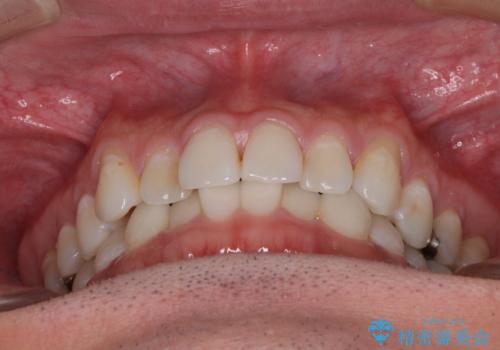

- 上下前歯の叢生を気にして来院された患者様です。

費用を抑え、期間もあまりかけずに治療をしたいとのことで、インビザライン・ライトを用いて矯正治療を行うこととしました。

インビザライン・ライトは、製作できるアライナーの枚数に制限があるため、移動可能な量に限りがあります。

一方で、半年から1年程度で治療を終えることができるため、軽度の歯列不正の患者様には大変お勧めです。